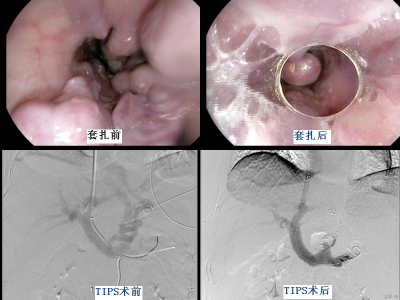

患者李某,男,44岁,有“乙肝”家族史。4年前因腹胀在当地医院诊断为“乙型肝炎后肝硬化失代偿期”。4年来反复因食管曲张静脉破裂出现呕血、黑便症状,于当地医院经“止血、输血、补液”等治疗后均可暂时血止。2015年春节前夕,患者再次出现大量呕血、黑便,在当地医院抢救治疗时行右侧股静脉置管,3天后出现右下肢肿胀,经B超检查诊断为右下肢深静脉血栓形成,遂转入我院消化内科。转入我院后,消化内科董蕾主任医师、戴社教主任医师及袁佳博士反复论证,为预防下肢深静脉血栓脱落形成致死性肺栓塞,遂行下腔静脉滤器置入术。术后经对症治疗患者右下肢肿胀明显减轻。为预防再次发生上消化道出血,消化内科为患者行胃镜下食管曲张静脉套扎治疗。套扎治疗10天后患者因套扎环脱落再次发生消化道大出血,呕血、便血量达到1000ml以上。经积极纠正休克治疗,患者生命体征平稳后,由消化内科戴社教主任医师、袁佳博士为患者实施了急诊经颈静脉肝内门体分流术(TIPSS)。术后患者恢复良好,未再发生消化道出血,已于近日出院。

上消化道大出血是危及肝硬化门静脉高压患者的头号杀手。我院消化内科目前开展多种方法治疗肝硬化上消化道出血,主要包括:药物治疗、内镜下治疗及TIPS治疗。TIPS全称为经颈静脉肝内门体分流术,是缓解肝硬化患者门静脉高压、治疗与预防消化道出血的最为有效的微创介入措施。相比于其它治疗方法,TIPS具有创伤小、效果好、恢复快等优点。我院消化内科近年来已常规开展该项手术。其原理是在门静脉与肝静脉或下腔静脉之间以覆膜支架建立分流道,使门静脉血流沿分流道顺利流向下腔静脉,缓解门静脉血液淤滞、降低门静脉压力。术中除建立门-腔静脉分流道外,还可同时栓塞因门静脉高压形成的食管胃底曲张静脉,达到“既疏又堵、双管齐下”预防消化道出血的目的。